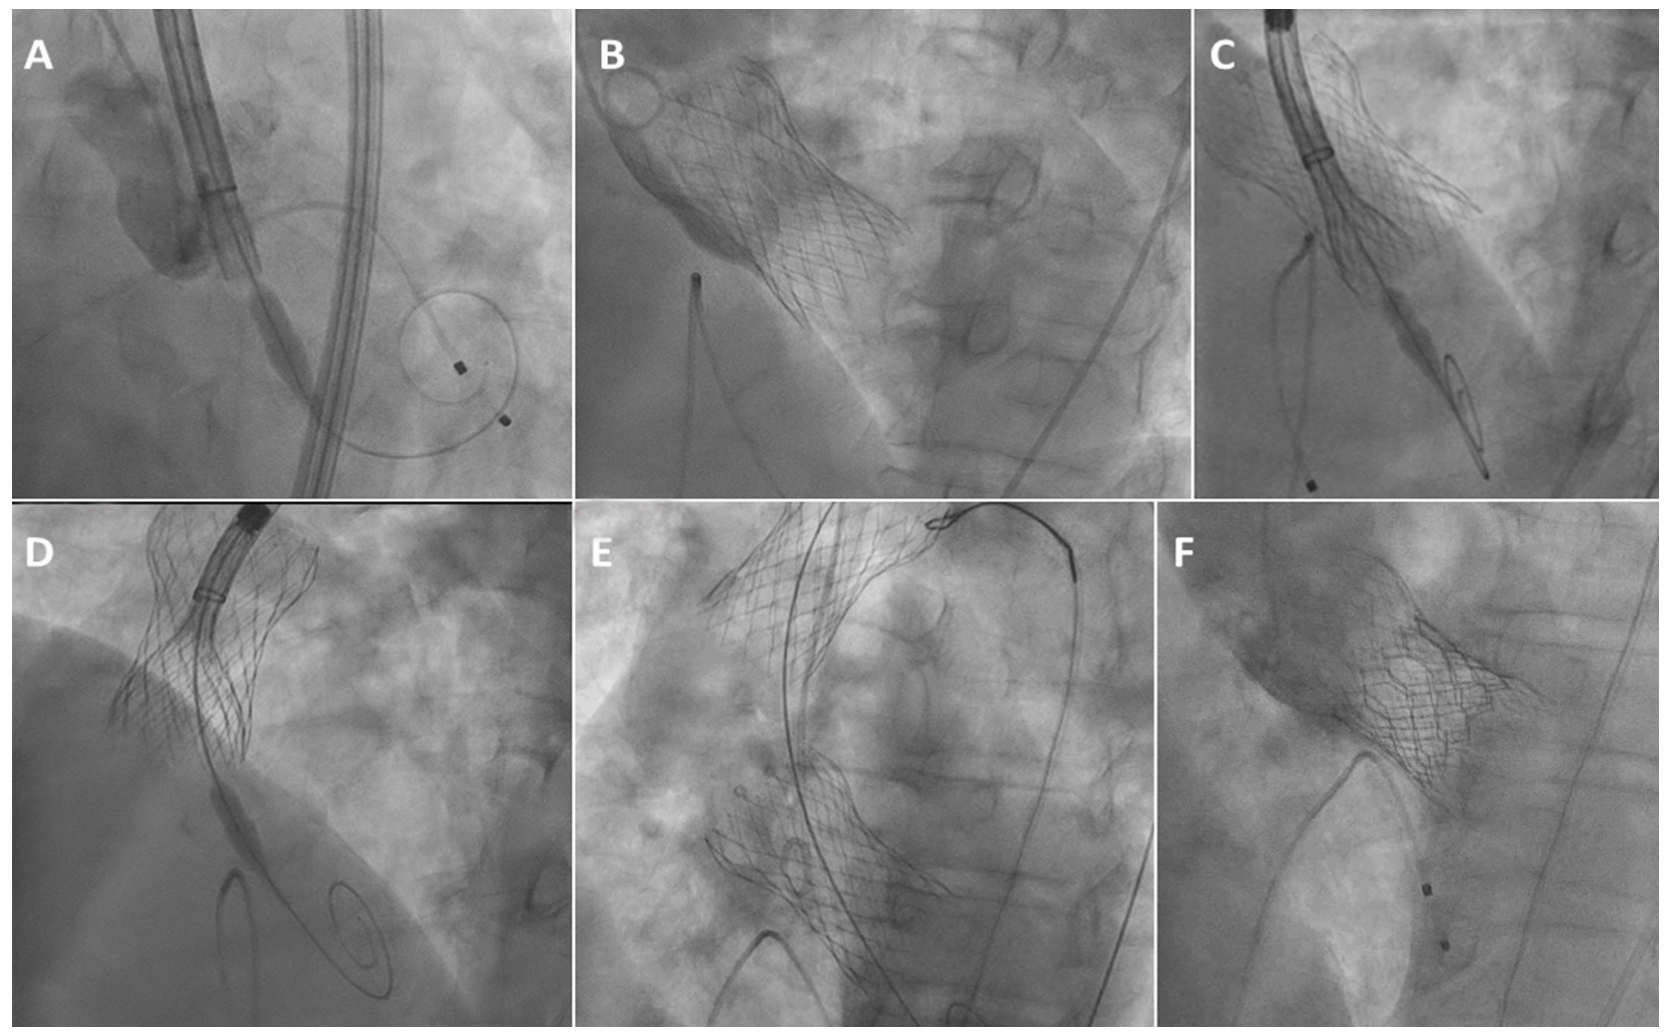

A 75-year-old male with severe symptomatic aortic stenosis and a hypertrophic and hyperdynamic left ventricle (Video 1) underwent TAVR. Annular perimeter and area were 78.7 mm and 472 mm2, respectively. Attempts to deploy a 29 mm Evolut-Pro valve at a depth of 5 mm below the annulus (Figure 1A) resulted in migration to the aorta (Video 2), requiring re-sheathing. The valve was finally deployed 16 mm below the annulus, resulting in severe aortic regurgitation (AR) due to location of the entire impermeable skirt within the left ventricular outflow tract (LVOT) (Figure 1B, Video 3). Attempt to implant another identical valve within the first valve at a higher position in order to seal the paravalvular leak by overlapping the device skirts and the annulus1 (Figure 1C), resulted in embolization of both valves to the aorta (Figure 1D, Video 4). The external valve was snared and pulled to aortic arch while the internal valve was re-sheathed and implanted 16 mm below the annulus, resulting in severe AR (Figure 1E, Video 5). A 26 mm Sapien S3 valve was then delivered (Video 6) and implanted within the second Evolut-Pro valve at the level of the aortic annulus, achieving a good hemodynamic result with trivial AR (Figure 1F, Video 7).

We initially selected a repositionable self-expanding valve to enable re-sheathing in case of valve migration,2 however valve anchoring within the hyperdynamic and hypertrophic left ventricle was not possible. Deep positioning of the second valve within the LVOT provided an anchor within which the third valve was successfully implanted at an intra-annular position.